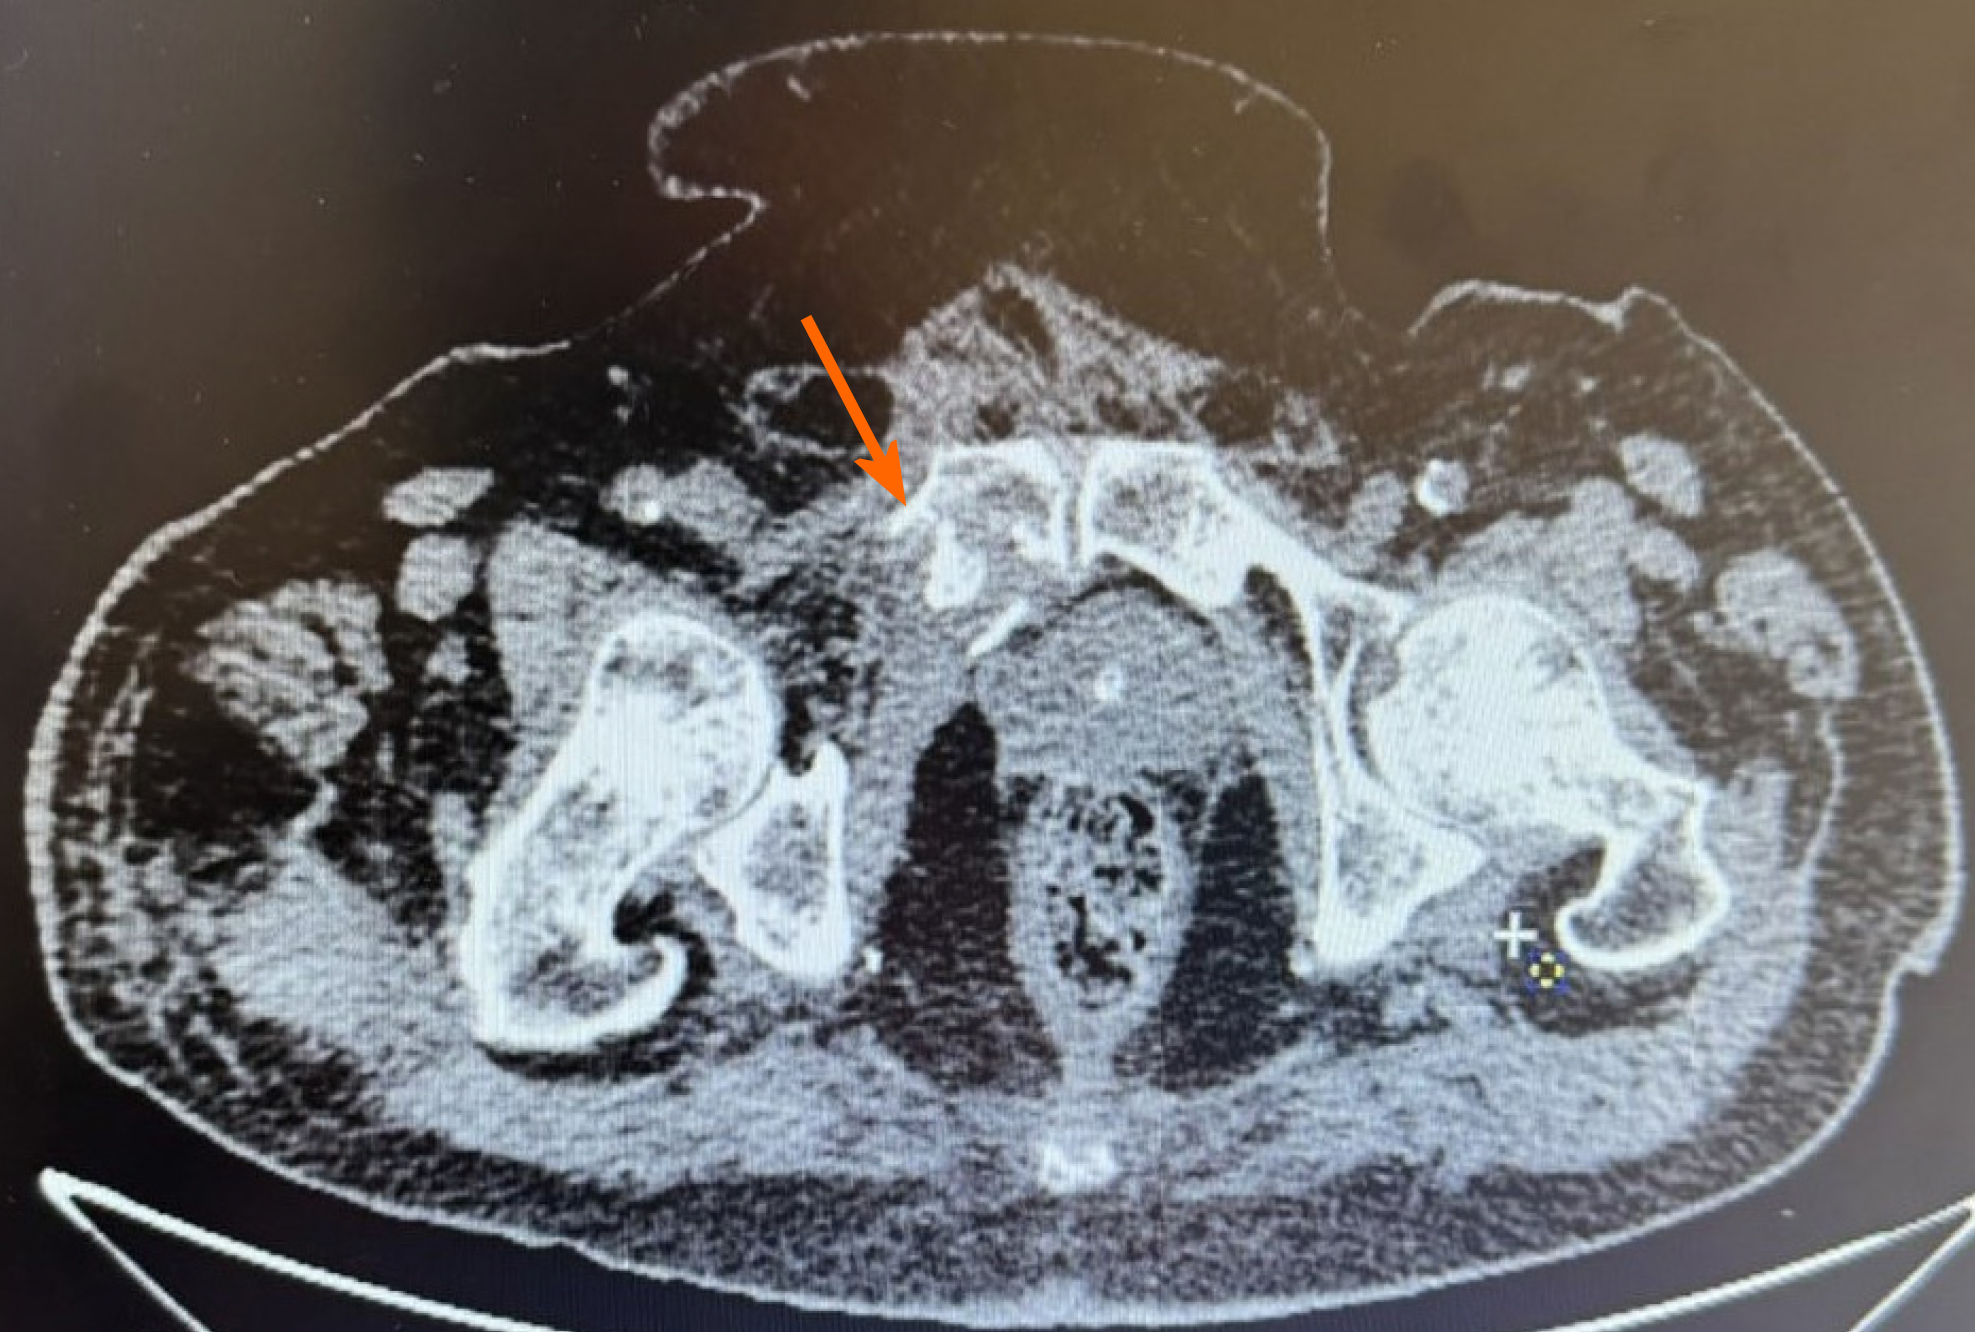

A plain pelvis X-ray was carried out, demonstrating an isolated right superior pubic ramus fracture (Figure 1). Forthwith after the initial diagnosis of the injury, a pelvis computed tomography (CT) scan was conducted for more rigorous evaluation of the fracture (Figure 2). No considerable hematoma was observed at this CT scan.